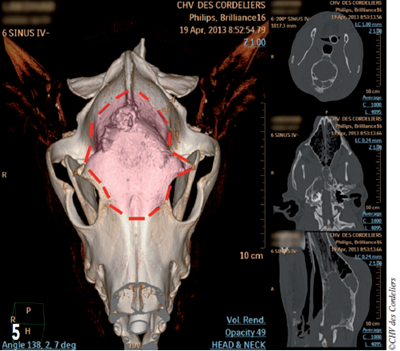

Une crâniotomie est réalisée en prenant des marges de 5 à 10 mm autour de la masse (photo 5).

Photo 5 : Délimitation de la craniotomie (en rouge) sur la vue tomodensitométrique préopératoire.

Les sinus frontaux sont ouverts puis les os frontaux, pariétaux et occipital sont coupés pour permettre la résection de la tumeur (photos 6a et 6b).